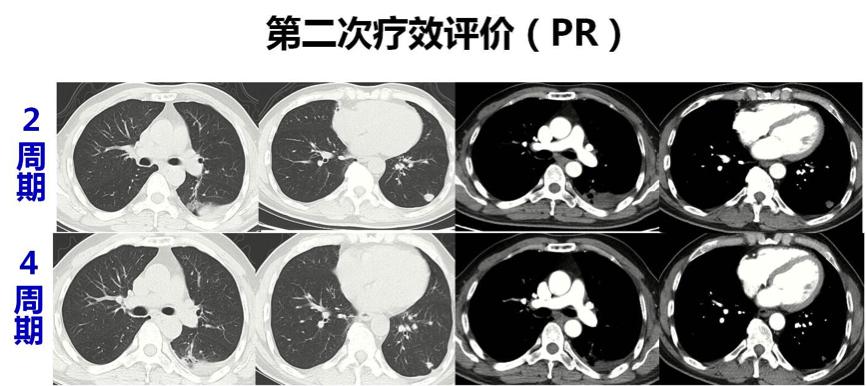

患者共完成6周期恩度联合AIM方案治疗,增强CT检查提示肺转移瘤较4周期后无明显改变,疾病稳定。

患者经过4个周期化疗以后,有明显的病灶缩小,体积下降超过75%。考虑到转移灶靠近胸膜,为外周型,有手术切除的可能,我个人认为目前可以进行外科手术切除,为患者创造二次缓解的机会。术后应继续化疗4-6周期。